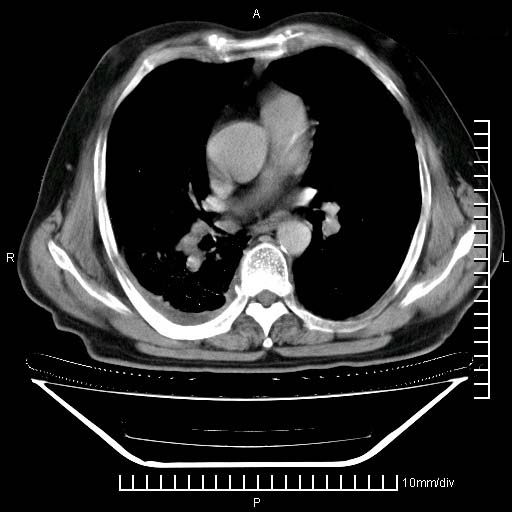

标题: CT24043:胸部增强:男性,60岁

既往肺结核,近10几天,咳嗽,咳痰,右侧胸痛,疼痛较明显,右上肺斑块考虑结核灶胸膜粘连,增强,可惜动脉期没有定好,未见强化,可延迟4分后又见较明显强化,中心见低密度影,如果说结核是边缘强化,可这个灶强化的面积挺大的,让人很挠头。

延迟4分后

强化的组织可能是膨胀不全的肺组织或炎性肉芽组织。

1)两肺继发性肺结核。2)右侧胸膜增厚+少量胸腔积液。